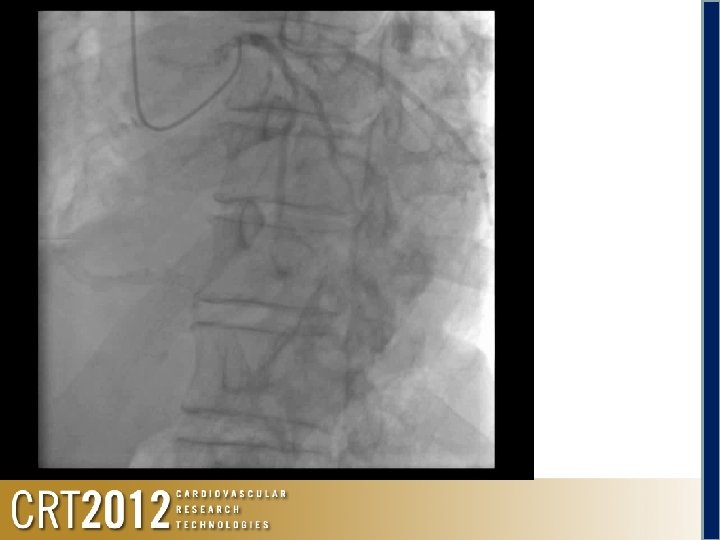

Occluded abdominal aorta Abdominal aorta occlusion

Shunt for hemodialysis 6 F SAL for RCA 6 F EBU for LCA Occluded abd aorta